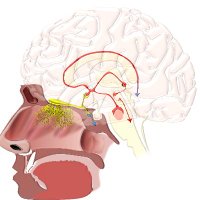

⭕️MCA occlusions / 🧠 infarct patterns Maybe time for this👇again Andrew Micieli? #MedTwitter #MedStudentTwitter #MedEd #FOAMed #neurotwitter #Neurology #stroke #Neurosurgery #EndNeurophobia #FOAMrad #NeuroRad #neuroradiology #radiology #radres #RadEd #FOAMncc #MRI